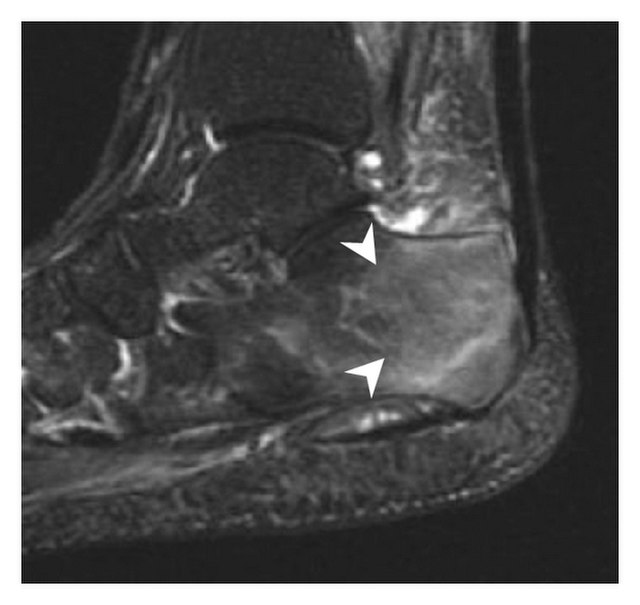

Scintigrafi eller MR:

Stressfrakturer: Anbefales for å identifisere mikrofrakturer og tidlige endringer som ikke er synlige på røntgen.